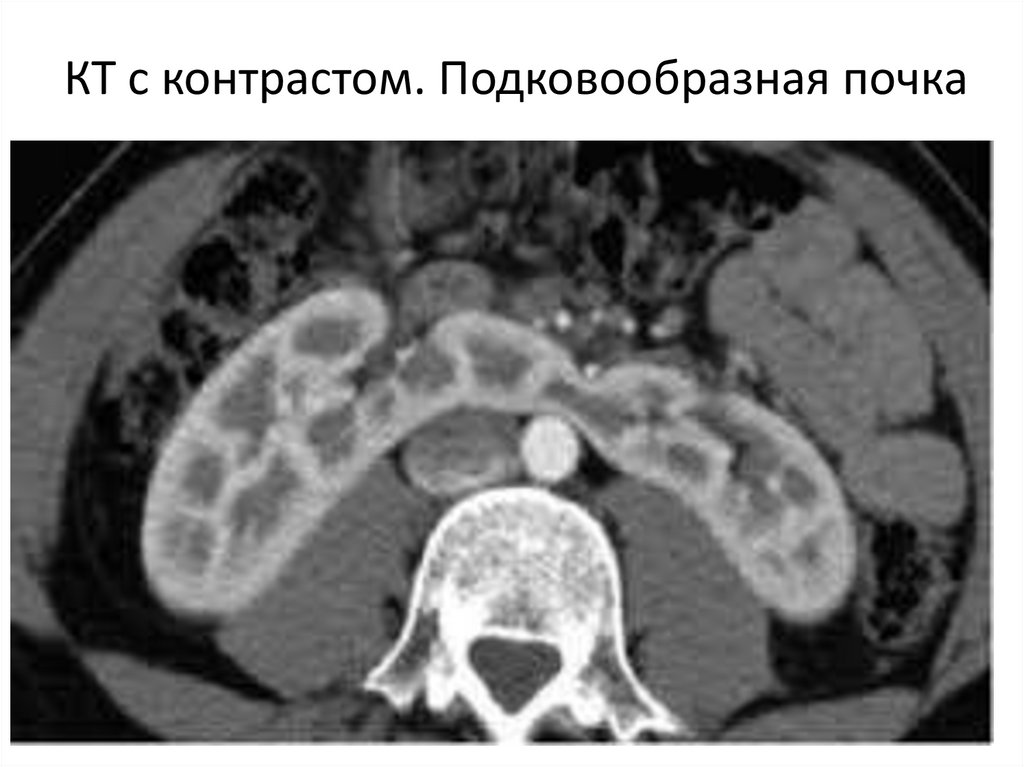

КТ с контрастом. Подковообразная почка

Аномалии сращения